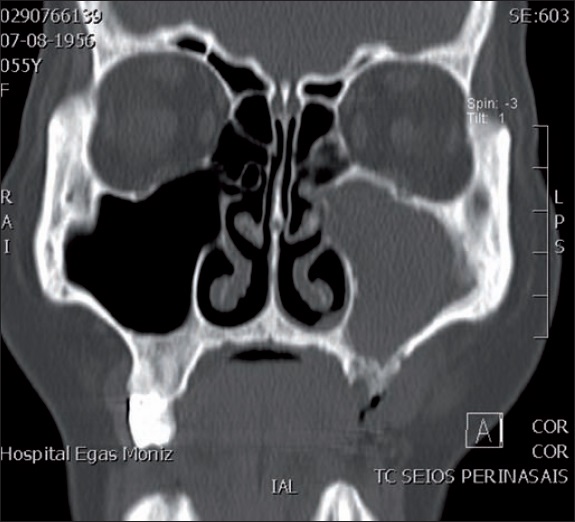

Al examen clínico observamos un defecto en el reborde alveolar de 3 mm de diámetro ( Fig. 1), confirmado en exámenes radiológicos (ortopantomografía y tomografía axial computarizada), con opacificación del seno maxilar y comunicación oroantral izaquierda, además de hipodensidad del cuerpo mandibular derecho ( Fig. 2). Establecimos así el diagnóstico de osteonecrosis por bifosfonatos de la hemimándibula derecha y del maxilar izquierdo, con fístula localizada a nivel del diente 26.